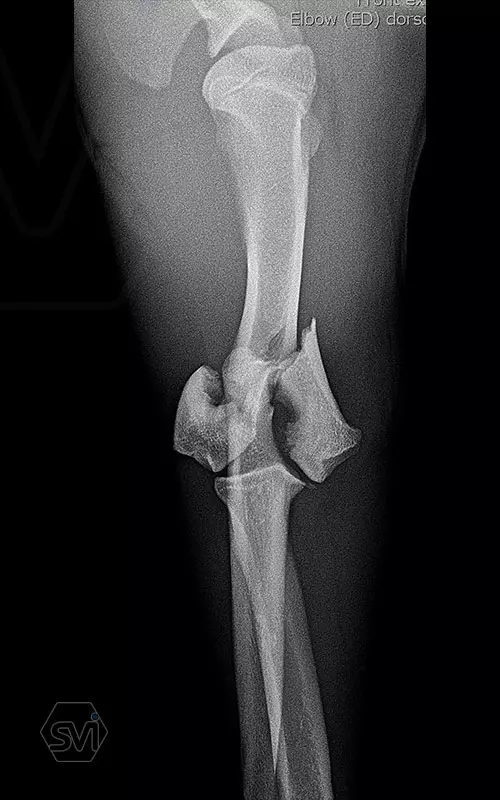

What used to be a nightmare type of surgery is slowly becoming my favorite: the humerus distal Y fracture

Yesterday, we operated on a Y fracture of the humerus of a 9-month-old French bulldog dog, where we used a cutable mini polyaxial straight plate (material thickness 2.0mm) and 2.4 polyaxial screws.

The fracture was favorable, the bone was not too fragmented, so we were able to plate the medial side easily, then turning the dog over, we replaced the lateral fragment as well and fixed it with a 2.4 intercondylar lag screw and with a shorter stright plate . It was very easy to work with the new plate, the surgery time was less than 2 hours. The stability is there, we placed a blind plug (screw head) in the lateral empty holes so that there is no weak point on the plate. The plate has mini polyax holes in which 2.4 and 2.0 polyax screws can be inserted (mini, 2.0-2.4 polyax system).